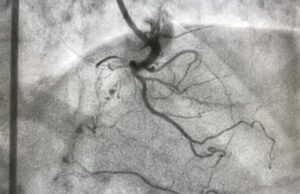

Artériographie

L’artériographie est un examen aux rayons X des artères. Il est réalisé par un radiologue qui va placer dans ...